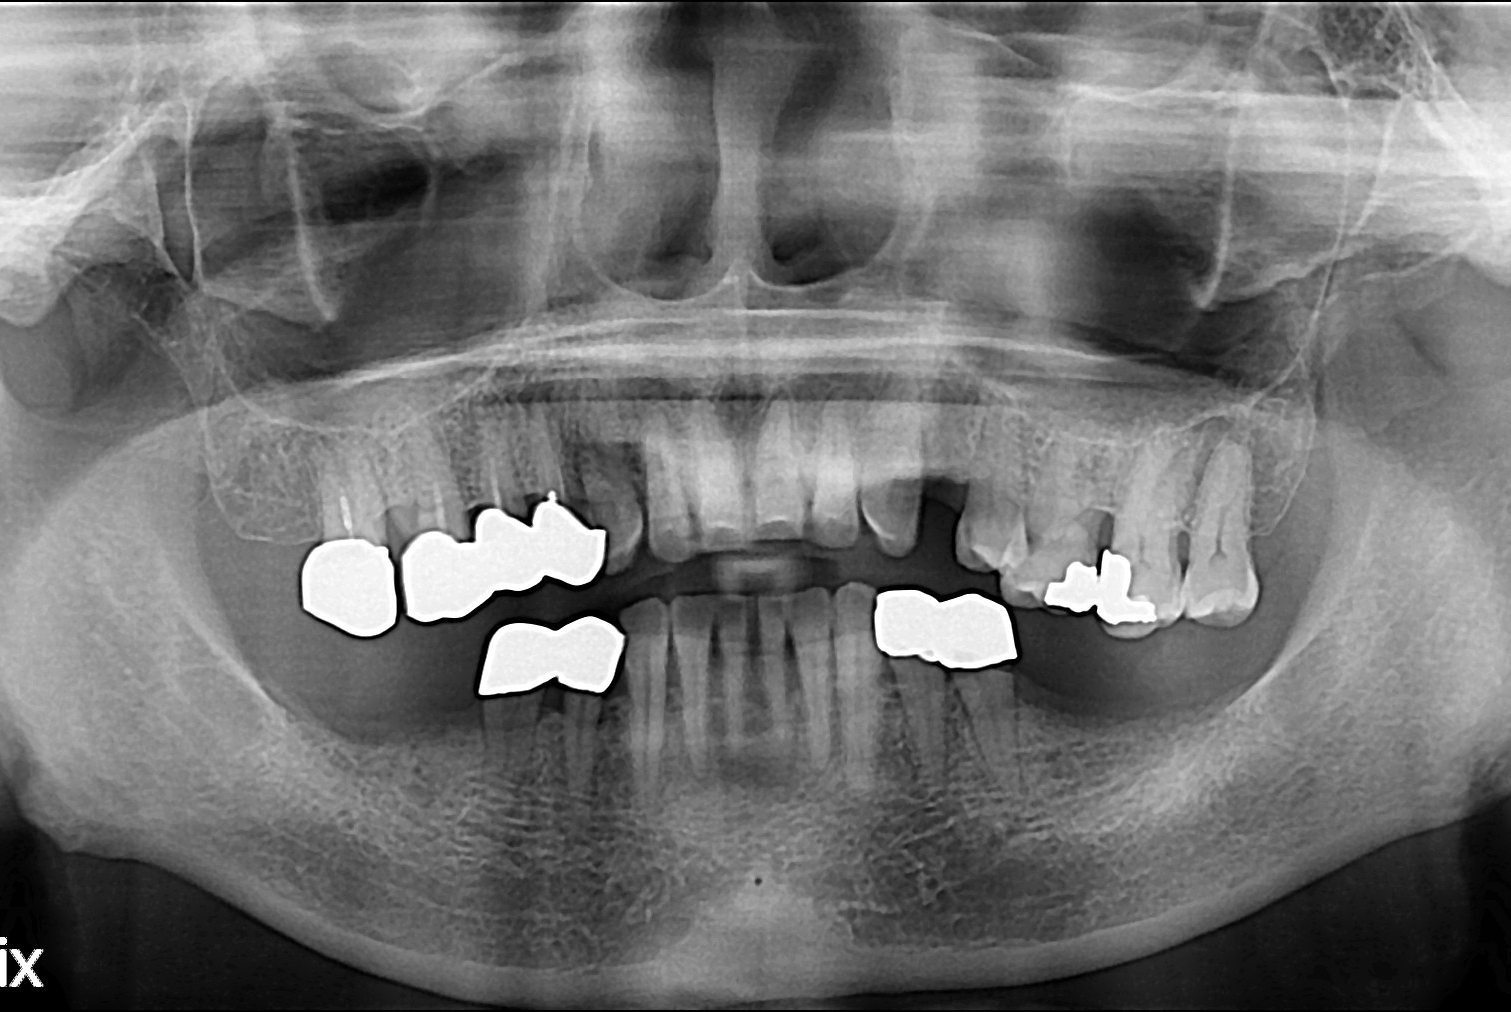

치료전 : 2016-08-26

치료후 : 2016-12-14

세종치과는 많은 환자와 다양한 케이스를 바탕으로 항상 편안한 임플란트 수술을 제공하고자 노력하고,

오래동안 튼튼히 쓸 수 있는 임플란트 수술을 가장 큰 목표로 삼고 있습니다